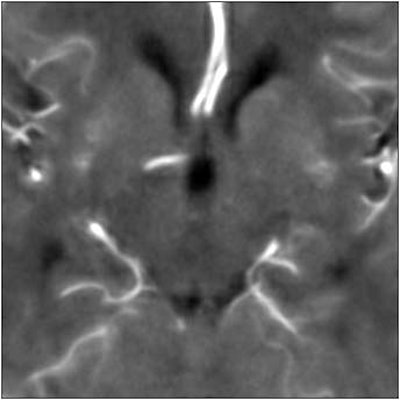

Finally they tested an anisotropic filter, which treats different image vectors differently. Anisotropic filters use the magnitude of local intensity gradients to determine which object edges should be preserved compared to less significant gradients.

In contrast, the anisotropic filter preserved 96% of the arterial signal, while overestimating blood volume by just 4%. Visually, the tissue and vasculature were both clearly delineated.

"The better the edges are preserved, the smaller the infarcts that you're able to detect," Quist said.

| Top image: original CT perfusion data shows brain parenchyma and opacified blood vessels (white), as well as substantial image noise. Middle image: same CT data after Gaussian filtering, which reduces image noise, but also reduces signal intensity in the blood vessels and distorts the signal in areas surrounding the vessels. Bottom image: Same data following application of anisotropic filter, which reduces image noise while preserving tissue boundaries. The boundaries are preserved by elongating the filter in a parallel orientation with the edges, such that the filter remains sufficiently large for appropriate noise reduction, but avoids mixing of several tissue types. All images courtesy of Marcel Quist. |

"There's one winner here, and the anisotropic filter performs best overall," he said. "Overall signal preservation is essential for quantitative analysis, and that's why we have included this anisotropic filter in our software."